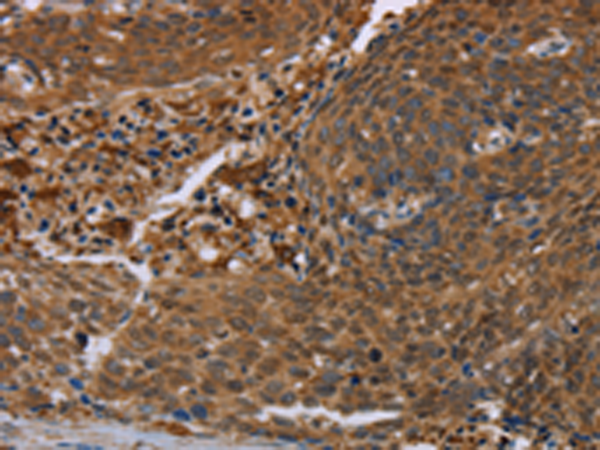

分类: 科研抗体货号: P04879别名: ATOD2应用: IHC反应种属: Human